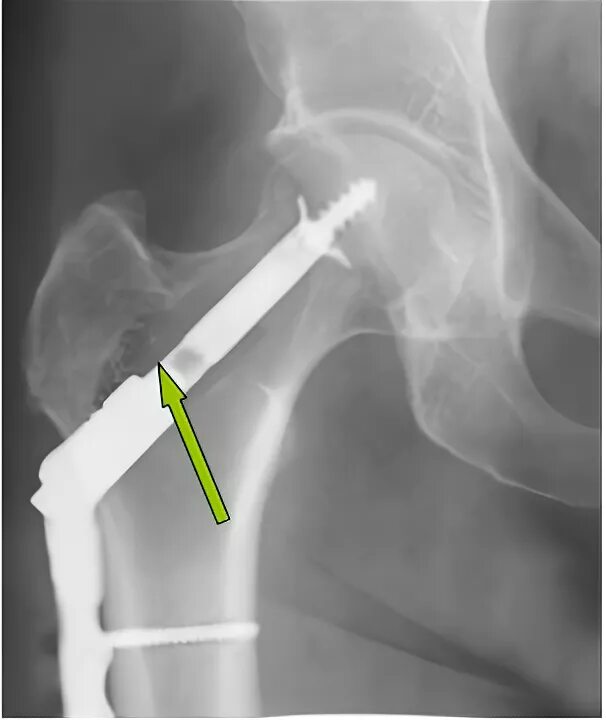

Чебоксары операция тазобедренного сустава